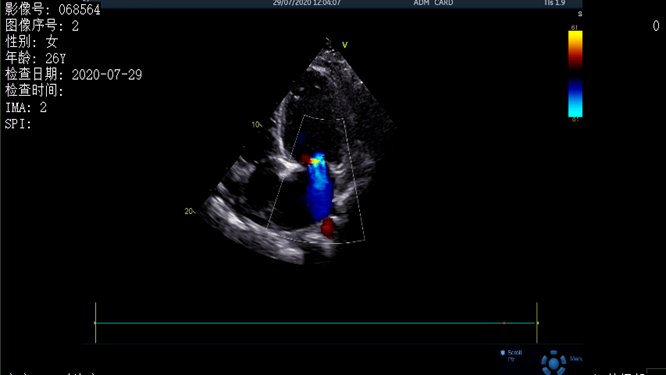

超聲結(jié)果顯示患者存在心包積液